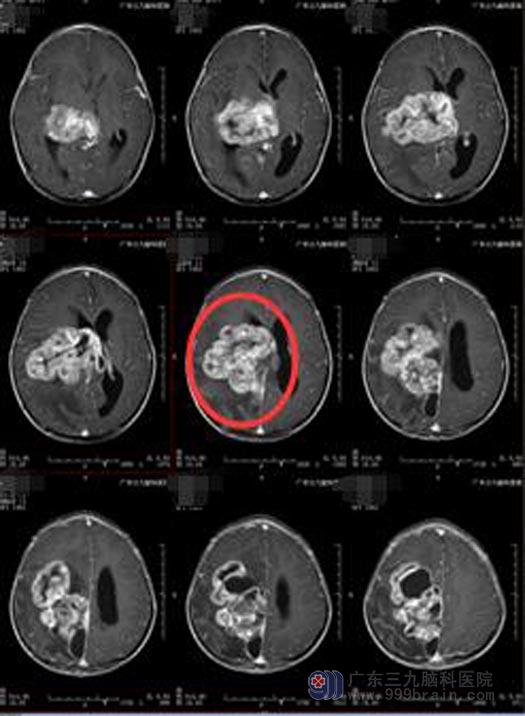

头颅CT提示:右侧丘脑-额顶叶巨大占位性病变,考虑肿瘤病变可能性大。由于手术难度非常大,小琪父母经多方打听,来到广东三九脑科医院综合神经外科。入院后,立即进行了进一步的检查:右侧丘脑-额顶叶囊实性占位性病变,病变范围约为8.4cm×7.1cm×8.7cm。